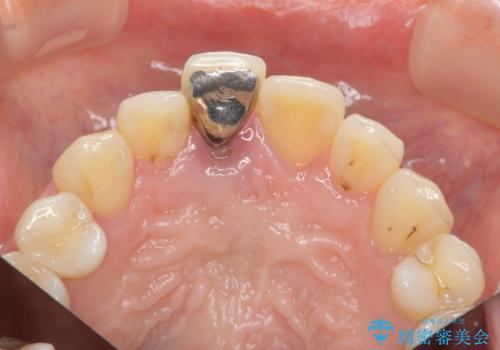

- 幼少期に前歯をぶつけて歯が折れ、神経の治療・クラウン治療を行った。グラつきと見た目の改善を希望して来院されました。

精密な仮歯をいれ、歯周組織を整えるとともにファイバーコア築盛、シェードテイキングを行い見た目に自然なジルコニアクラウンを製作していきます。